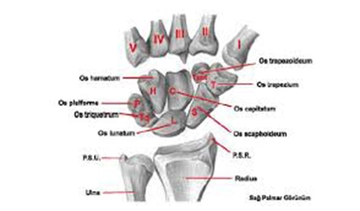

Tanı YöntemleriEl bileği burkulmasının teşhisi genellikle fizik muayene ve görüntüleme yöntemleriyle yapılır. Doktor, aşağıdaki yöntemleri kullanarak tanıyı koyabilir: